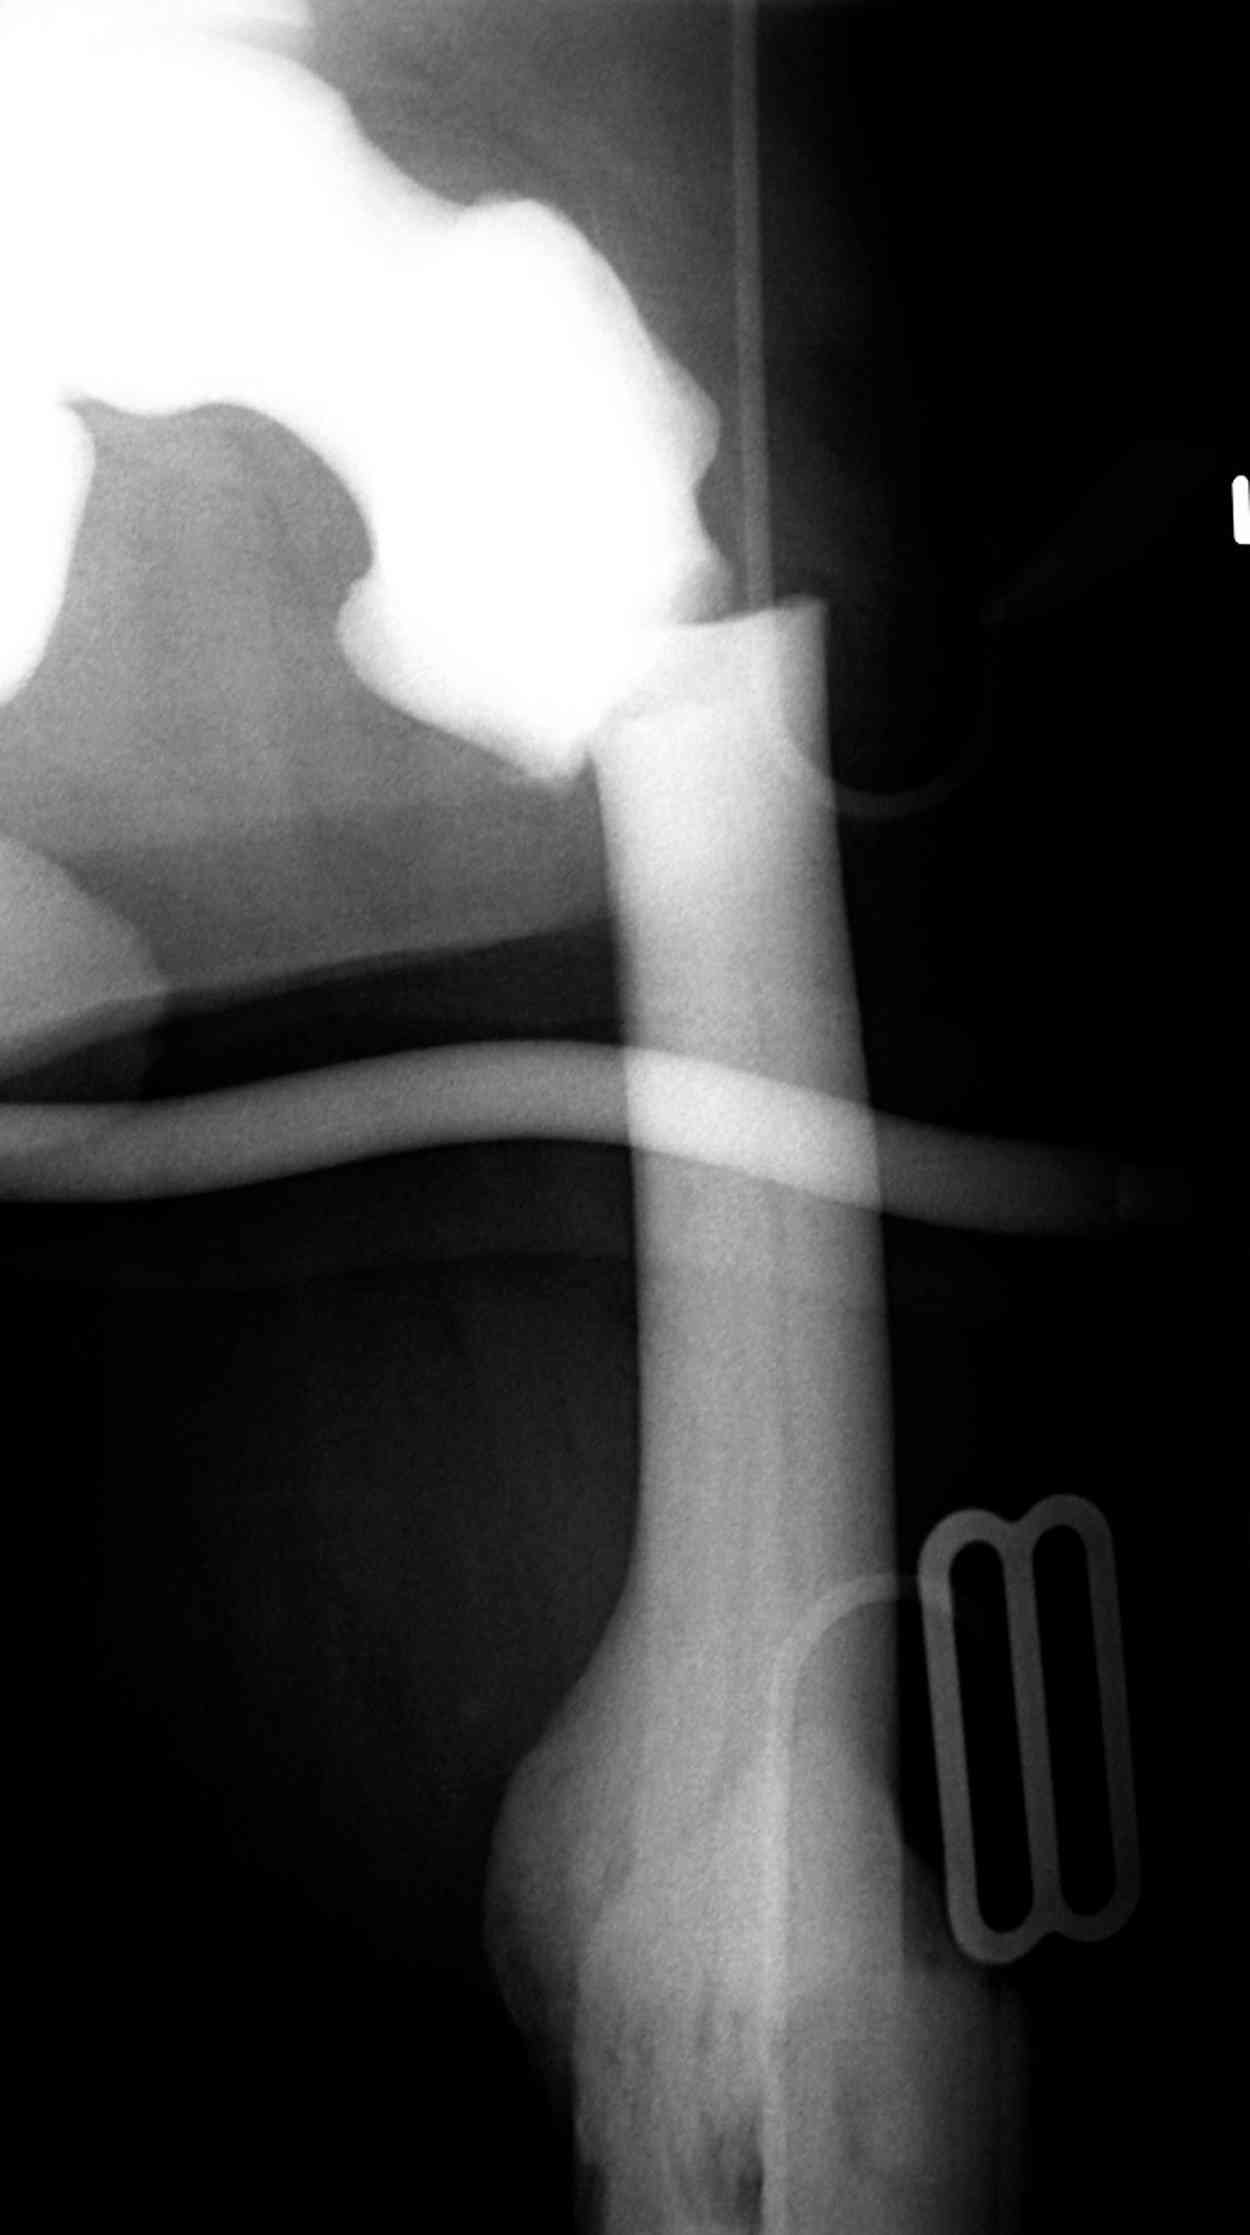

Уважаемый Константин Иванович! Полностью согласен с проф. Михайловым, данный случай не похож на мраморную болезнь, при которой имеется резкое, строго симметричное и генерализованное уплотнение костной ткани (остеопетроз), и кость оказывается построенной преимущественно из гомогенного компактного костного вещества. Для примера привожу случай из архива нашего института (бедренные, плечевые кости и таз, рис 1,2,3)

Изменения структуры костей у Вашего пациента больше похожи на полиоссальную форму фиброзной дисплазии или болезнь Педжета, возможены также инфаркты костного мозга б.берцовых костей. К сожалению, качество снимка не очень хорошее, непонятно, сохранен ли кортикальный слой б.берцовых костей по передней поверхности.

слайды из прошлегодного случая.